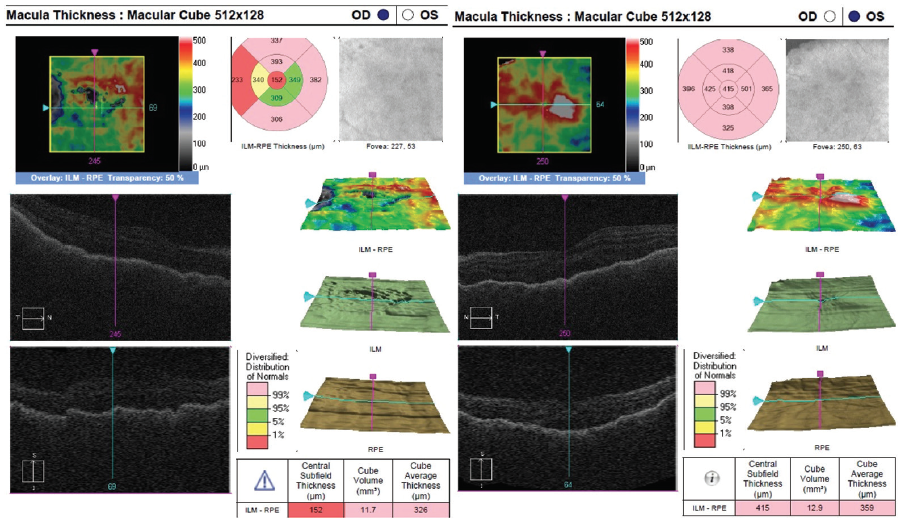

Dilated fundus examination revealed clear media without inflammation OU and numerous deep, discrete, and patchy yellow lesions throughout the posterior pole with irregular borders and multiple areas of distinct retinal elevation OU (Figure 1). The optic nerves were noted to be hyperemic OU without significant elevation, hemorrhage, or obscuration of vessels. Of note, there was no evidence of peripheral pathology or retinal vasculitis. OCT imaging showed numerous areas of intraretinal and subretinal fluid pockets of varying size with notable retinal and choroidal undulation through the macula (Figure 2). Fluorescein angiography showed multiple irregular patchy and pinpoint areas of hyperfluorescent foci throughout the posterior pole with leakage and distinct pockets of pooling in the later frames (Figure 3).

Figure 1. Color fundus photography on presentation shows numerous subretinal discrete yellow lesions throughout the posterior pole with irregular borders and multiple areas of distinct retinal elevation OU.

Figure 2. OCT shows multiple pockets of intraretinal and subretinal fluid with undulation of the retina and choroid OU on initial presentation.